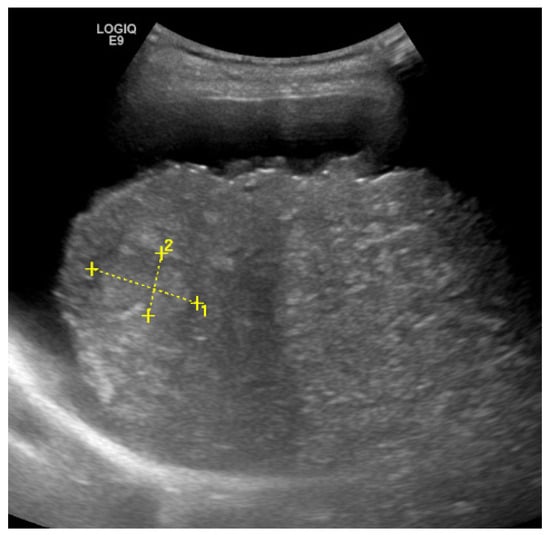

2. Detection and Graduation of Hepatic Steatosis

| B-Mode US [14,15,16,17,18] | 53–76% | 76–93% | -High availability -high-end-device not required | -semiquantitative -low sensitivity for mild steatosis (<30%) |